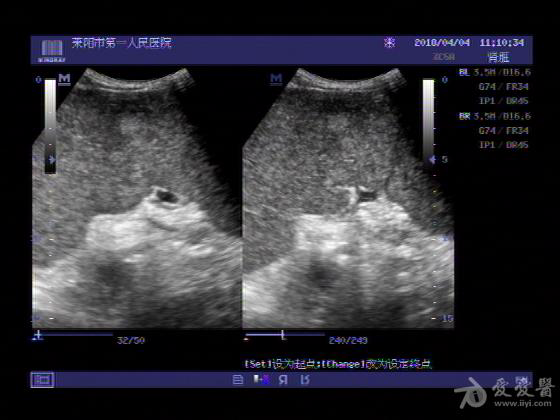

超声入门贴755脾肿瘤并脾大腹腔积液